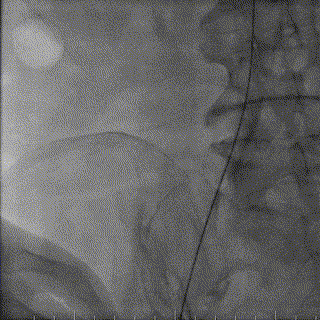

18m*40mm瓣膜球囊扩张导管,起搏160bpm,行球囊扩张。

18x40mm球囊预扩